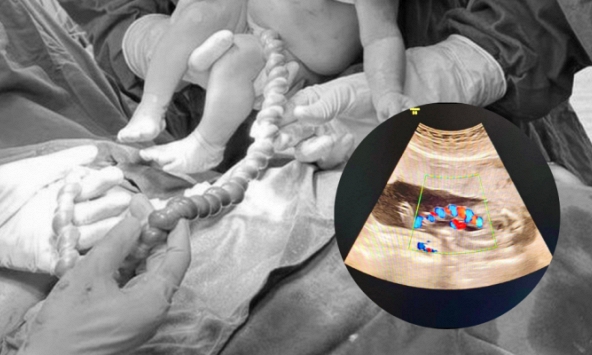

Qua thăm khám, các bác sĩ Phòng Khám cấp cứu xác định, người bệnh chuyển dạ đẻ lần 1, song thai 36 tuần 6 ngày tuổi. Thai A ngôi ngược, ối vỡ sớm, suy thai cấp do sa dây rốn/người bệnh thực hiện kỹ thuật IVF. Đây là trường hợp khẩn cấp, nguy cơ mất tim thai nhi có thể tử vong; mẹ nguy cơ băng huyết, chảy máu, đờ tử cung, nguy hiểm đến tính mạng. Bác sĩ Phạm Thị Vân lập tức báo động đỏ toàn viện; cho chuyển người bệnh lên cáng, dùng tay đẩy ngôi thai lên cao, chuyển phòng mổ cấp cứu.

Tại phòng mổ, BSCK2.Nguyễn Thị Vân, Phó trưởng Khoa Quản lý thai nghén và Chẩn đoán trước sinh (trực cột 1) cùng các bác sĩ gây mê hồi sức, sơ sinh… có mặt đầy đủ, chỉ trong vòng 5 phút, các bác sĩ khéo léo đưa được 2 bé trai với cân nặng lần lượt 3.000gr, 2.900gr ra ngoài an toàn, không gặp biến chứng hay chấn thương. Hiện tại, sức khỏe của sản phụ cùng hai bé ổn định.

Theo các bác sĩ, cấp cứu sa dây rốn là cấp cứu hàng đầu trong sản khoa, có khả năng gây suy thai cấp vì việc cung cấp máu của dây rốn cho thai bị đình trệ do co thắt của các mạch máu dây rốn. Nếu không lấy thai ra ngay, sẽ nguy hiểm đến tính mạng của thai nhi.